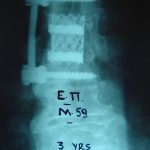

- α

- β

- γ

- δ

Εικ. 6: Μετεγχειρητικές ακτινογραφίες (α,β) 3 και (γ,δ) 9 έτη μετά την επέμβαση

Παρατηρείται η σταθερότητα της σπονδυλικής στήλης και η ακεραιότητα των υλικών